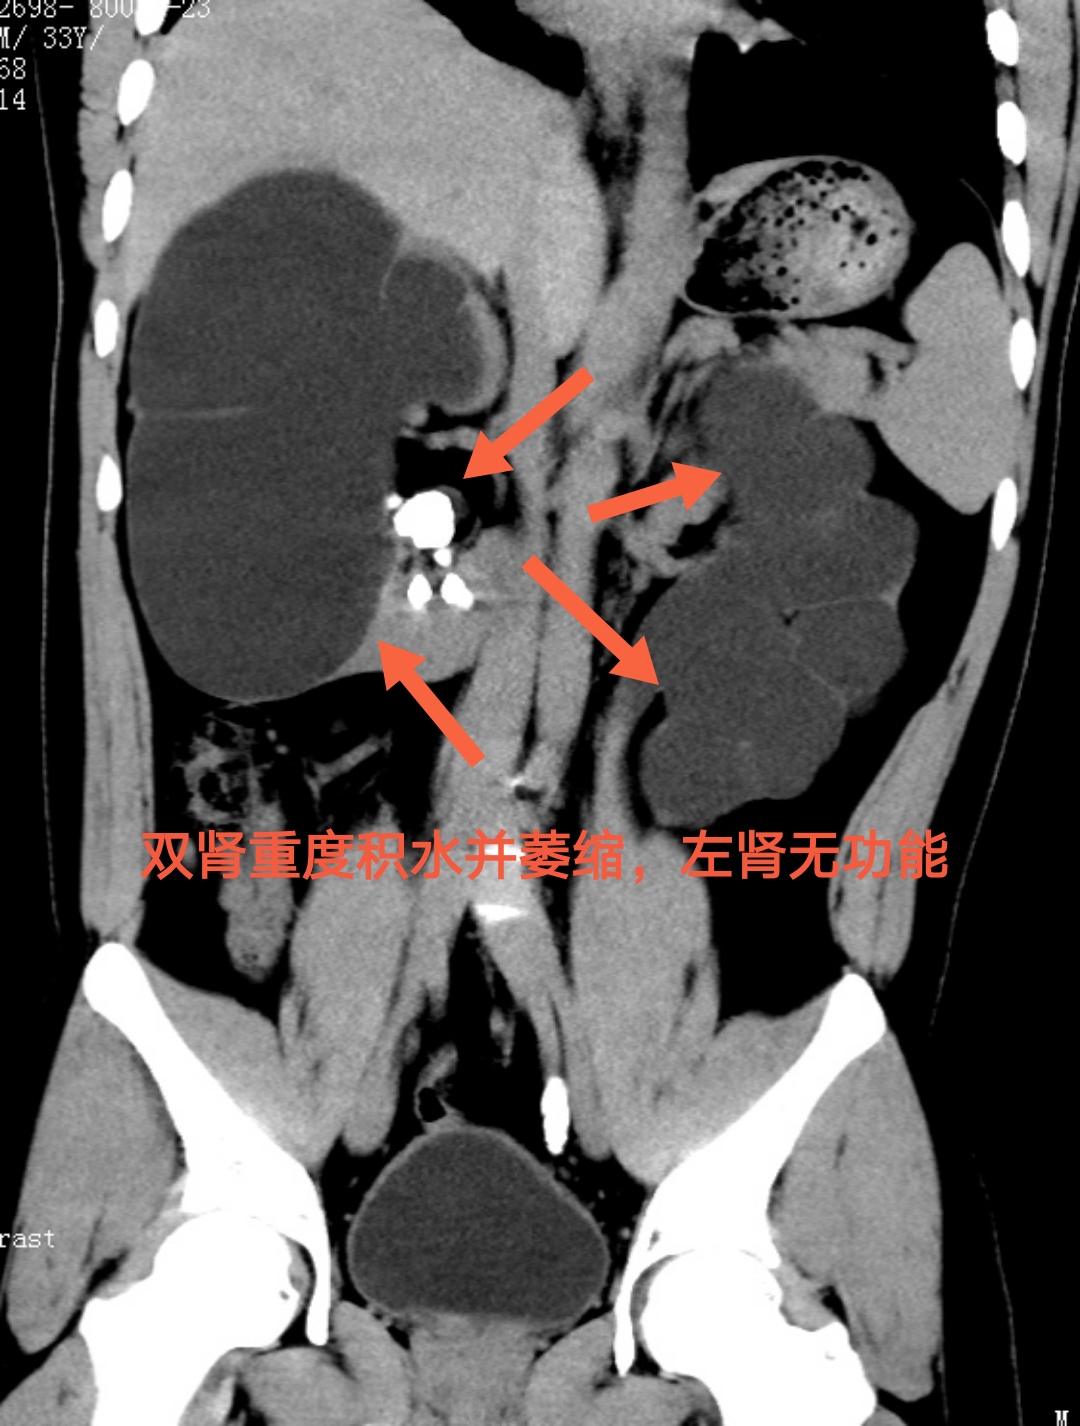

湖南益阳30岁的小申刚入职公司不久,平素身强体健,从未有过肾周不适及腰痛。这次,却在公司常规体检时发现双肾重度积水,这才赶紧到捷克论坛 泌尿四科就诊。

接诊的泌尿四科主任杨科详细询问病情,经进一步CT检查发现,小申的双侧肾输尿管里长了结石,严重肾积水是因为结石长期坎顿梗阻所导致的。由于没有任何症状,正值壮年的他也从未体检,并不知道结石在体内已对身体造成了伤害,长期下来,左肾已经完全丧失了功能。最终,小申在泌尿四科成功接受手术治疗,遗憾的是,他失去了一个肾。